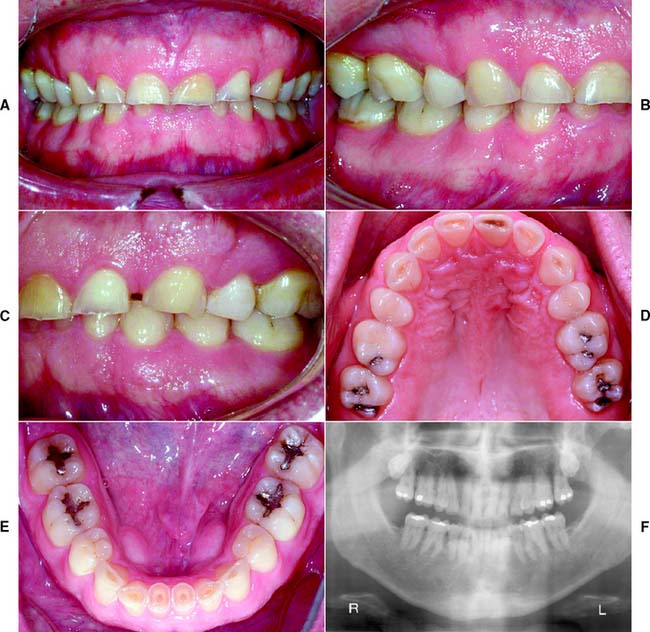

This class (Figs. 1-27 and 1-28) is characterized by ideal or minimal compromise in the location and extent of edentulous area (which is confined to a single arch), abutment conditions, occlusal characteristics, and residual ridge conditions. All four of the diagnostic criteria are favorable.

Fig. 1-27 Class I patient. This patient is categorized as Class I because of an ideal or minimally compromised edentulous area, abutment condition, and occlusion. There is a single edentulous area in one sextant. The residual ridge is considered type A. A, Frontal view, maximum intercuspation. B, Right lateral view, maximum intercuspation. C, Left lateral view, maximum intercuspation. D, Occlusal view, maxillary arch. E, Occlusal view, mandibular arch. F, Frontal view, protrusive relationship. G, Right lateral view, right working movements. H, Left lateral view, working movement. I, Full-mouth radiographic series.

(From McGarry TJ, et al: Classification system for partial edentulism. J Prosthodont 11:181, 2002.)

Fig. 1-28 Class I patient. The patient is categorized as Class I because an ideal or minimally compromising tooth condition, and occlusal scheme is exhibited. A single large amalgam core restoration requires a complete coverage restoration in one sextant. A, Frontal view, maximum intercuspation. B, Right lateral view, maximum intercuspation. C, Left lateral view, maximum intercuspation. D, Occlusal view, maxillary arch. E, Occlusal view, mandibular arch. F, Panoramic radiograph.

(From McGarry TJ, et al: Classification system for the completely dentate patient. J Prosthodont 13:73, 2004.)

The edentulous area does not compromise the physiologic support of the abutments.

The edentulous area may include any anterior maxillary span that does not exceed two incisors, any anterior mandibular span that does not exceed four missing incisors, or any posterior span that does not exceed two premolars or one premolar and one molar.